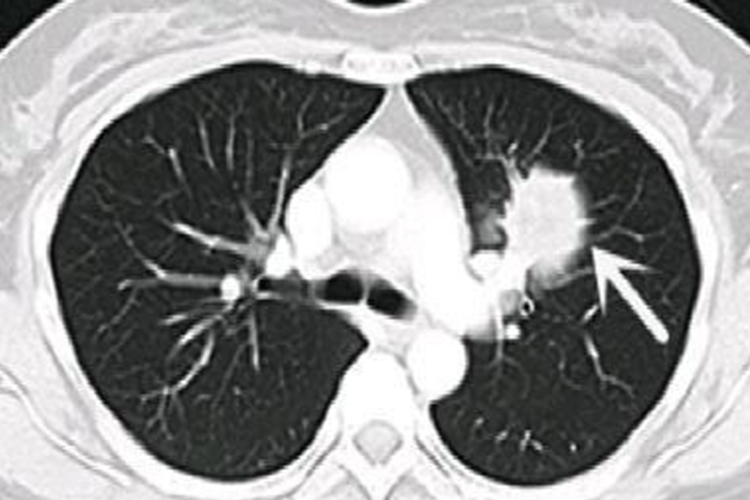

肺部霉菌感染

肺部霉菌感染可无明显呼吸道症状,但可因合并细菌感染出现明显的咳嗽、咳痰、发热等表现。影像学检查可发现肺内散在分布大小不一的小结节,并晕轮的块状影、多个透明空洞。